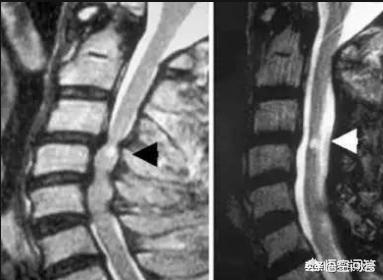

Les symptômes de la spondylose cervicale sont illustrés dans le diagramme ci-dessous.

Dans la pratique clinique, il existe une catégorie de patients atteints de spondylose cervicale et de spondylose cervicale, appelée "spondylose cervicale spinale". Une fois le diagnostic posé, les patients doivent être immédiatement opérés, il n'est pas nécessaire d'envisager un traitement conservateur, car celui-ci n'aura aucun effet, mais ne fera que retarder la durée du traitement, ce qui affectera le pronostic.

L'incidence de ce type de spondylose cervicale est d'environ 15 %, et le taux d'invalidité clinique est extrêmement élevé car l'effet pronostique dépend du délai de traitement (la grande majorité des patients rejettent aveuglément la chirurgie et sont non seulement réticents à subir une intervention chirurgicale, mais aussi à se rendre à l'hôpital pour un examen, ce qui leur permet d'adopter facilement une mauvaise approche thérapeutique et de retarder le délai de traitement).

Ces conditions indiquent que la spondylose cervicale entraîne une forte compression nerveuse, soit sur les racines nerveuses, soit sur la moelle épinière, et pour ce type de compression réelle, il est souvent moins efficace de s'en remettre uniquement aux médicaments et à la physiothérapie. En outre, dans le cas d'une compression de la moelle épinière, c'est-à-dire d'une spondylose cervicale médullaire, la traction ou le massage peuvent même aggraver les symptômes et conduire à la paraplégie.